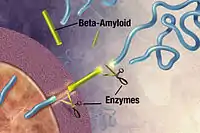

Alzheimer's disease has been identified as a protein misfolding disease (proteopathy), caused by plaque accumulation of abnormally folded amyloid beta protein and tau protein in the brain.[100] Plaques are made up of small peptides, 39–43 amino acids in length, called amyloid beta (Aβ). Aβ is a fragment from the larger amyloid precursor protein (APP). APP is a transmembrane protein that penetrates through the neuron's membrane. APP is critical to neuron growth, survival, and post-injury repair.[101][102] In Alzheimer's disease, gamma secretase and beta secretase act together in a proteolytic process which causes APP to be divided into smaller fragments.[103] One of these fragments gives rise to fibrils of amyloid beta, which then form clumps that deposit outside neurons in dense formations known as senile plaques.[97][104]